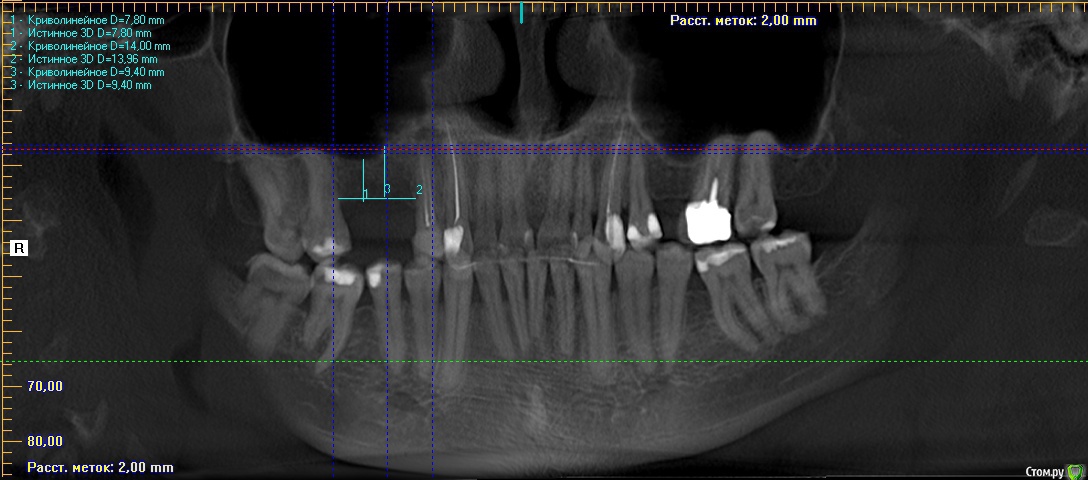

Дмитрий-Р Опубликовано 4 апреля, 2016 Поделиться Опубликовано 4 апреля, 2016 Здравствуйте, после 2-х консультаций немогу выбрать к кому идти. Ситуация такая: необходимы 2 импланта справа вверху (1,6 и 1,5). Год назад, в этом месте, были удалены два корня и осуществлена (сразу) пластика коллапаном. Врач №1. Синуслифтинг не нужен, ставим 1,6 (35 L=6 мм) и 1,5 (35 L=9 мм). Система Астра Техн. Врач №2. Сперва открытый синуслифтинг искусственной костью и одномоментно расширение десны (+подсадка ткани на впалую часть десны со стороны щеки). Системы 3-i? Impro, MIS, Inno. Подскажите пожалуйста, какой путь выбрать? Может быть искать 3-й вариант? Ссылка на комментарий

Дмитрий-Р Опубликовано 6 апреля, 2016 Автор Поделиться Опубликовано 6 апреля, 2016 Благодарю всех за ответы (особенно Доктор Хаус).Больше информации дать не могу, не владею программой просмотра мрт, вот поставил кривенько расстояния. Вопрос, который вытекает из ответов: на основе чего врач делает выбор между открытым и закрытым синуслифтингом? Закрытый может быть сложнее проводить, поэтому мне предложили открытый? Может быть наоборот? Или при закрытом меньше вероятность хорошего результата? Врач не очень кваллифицирован для закрытого? Или вобще другие причины Ссылка на комментарий